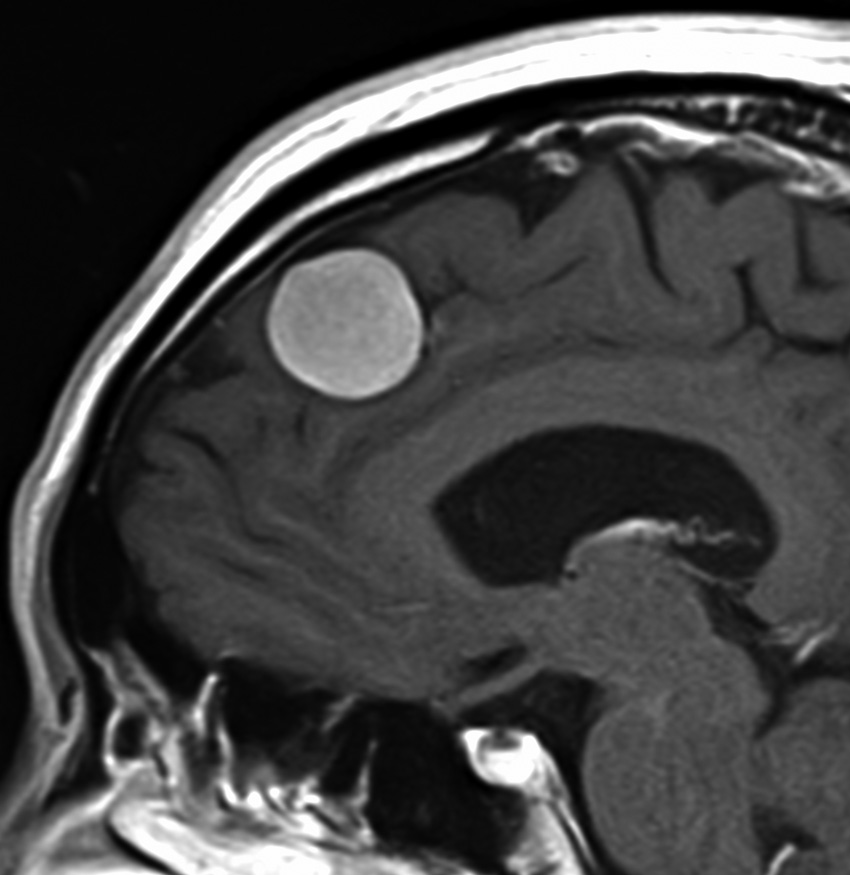

典型的な髄膜腫

この髄膜腫は中程度の大きさのものです。円蓋部髄膜種という最も多い最も手術の簡単なタイプです。麻痺や失語症やてんかんなどの症状はありません。とても美しくて若い女性の髄膜腫でしたが,子供に遺伝はしませんし,癌などと違ってタバコなどこれといった原因がなくて発生するものです。

MRIでの髄膜腫の見え方は撮影の仕方によっていろいろです。左からT1強調画像,T2強調画像,フレア画像といいます。腫瘍の横に小さく白い領域がありますが,これは脳の腫れた部分で脳浮腫といいます。髄膜腫があると周囲に脳浮腫が生じることがあります。

最も見やすいのが,ガドリニウム造影剤を注射して撮影するものです。一般的に髄膜腫は造影剤で白く映し出されます。この腫瘍は左脳側にあります。MRIの軸面という輪切りの写真では左右が逆になりますから注意してください。脳を下から見た図になっています。MRIはいろいろな方向から腫瘍を見ることができますが,右は冠状断という正面から見た図です。よく見ると腫瘍の上と下のはじっこに線状に糸を引いたように造影される部分があります。これをテールサイン(しっぽのサイン)といいます。腫瘍が硬膜に沿って延びている可能性があることを示しています。

手術後のMRIです。腫瘍は全部取れていて後遺症もありません。圧迫されて変形していた脳はきれいに元に戻っていますし脳浮腫も消えました。一般的に若い人の脳ほどきれいに元に戻ります。注意しなければならないのは,少しでも取り残した場合には,何年か後に10%-20%くらいで再発があることです。もちろん完全に取れた時の再発はほとんどありません。